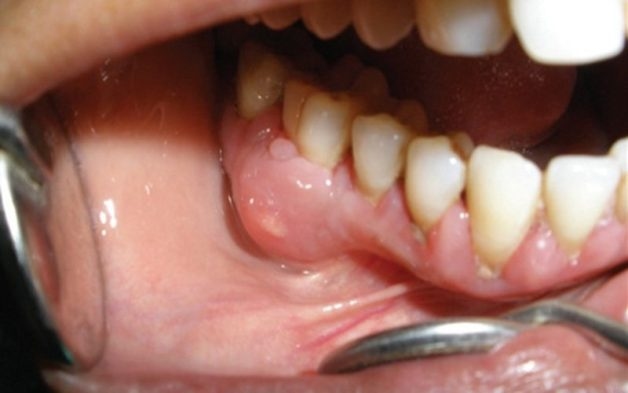

Một ổ áp xe do sâu răng

– Áp xe chân răng: Phần mủ tích tụ nhiều và hình thành nên các ổ áp xe gây nên các cơn đau nhức và viêm nhiễm tăng mạnh, lan sang các khu vực lân cận.